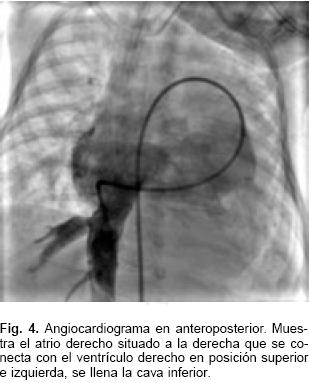

El estudio hemodinámico corroboró los diagnósticos y demostró que las presiones en ambos ventrículos, la arterial pulmonar y de la aorta eran las mismas; la presión sistólica sistémica fue de 50 mm Hg. Se evidenció una comunicación interventricular trabecular pequeña. El gradiente entre el arco aórtico y la aorta descendente fue de 17 mm Hg, con coartación aórtica yuxtaductal e hipoplasia importante del istmo aórtico y de la porción horizontal del arco; se confirmó la permeabilidad del conducto arterioso (Figs. 4, 5 y 6). La resonancia magnética nuclear hizo más relevantes las características anatómicas, para presentar el caso al Servicio de Cirugía (Fig 7).

Las conexiones atrioventriculares cruzadas se establecen cuando la posición espacial de los ventrículos no concuerda con la de los atrios con quienes están conectados, de tal manera que en el presente caso el atrio derecho situado a la derecha está conectado con el ventrículo derecho ubicado espacialmente a la izquierda y viceversa.2 Es constante, aunque no patognomónica, la posición superoinferior de los ventrículos debida a la ubicación horizontal del tabique interventricular. El término crisscross refiere una relación particular entre las entradas ventriculares y no describe al corazón de manera completa.6